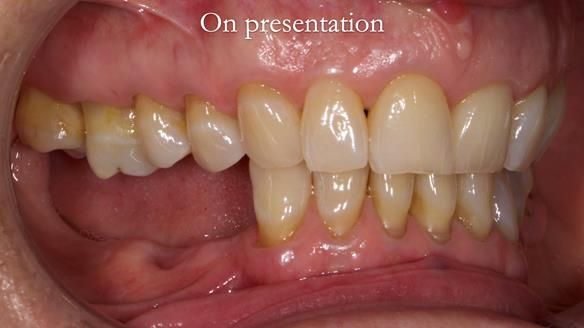

Joyce's Case Presentation 61

Welcome to Newsletter 61. In this edition, I walk through the process of creating and fitting a metal based lower partial denture for Joyce, a fit and healthy 76 -year-old woman.

Joyce self-referred to me for specialist prosthodontics.

“Lower right side teeth now all gone. They didn’t fill them back in 1958 – just pulled them”

The missing lower right teeth to be replaced with a metal based partial denture.

The detailed clinical situation and treatment process are outlined below, with clinical work provided by me and technical work by Rowan Garstang. The treatment spanned six visits for denture fitting and one review.